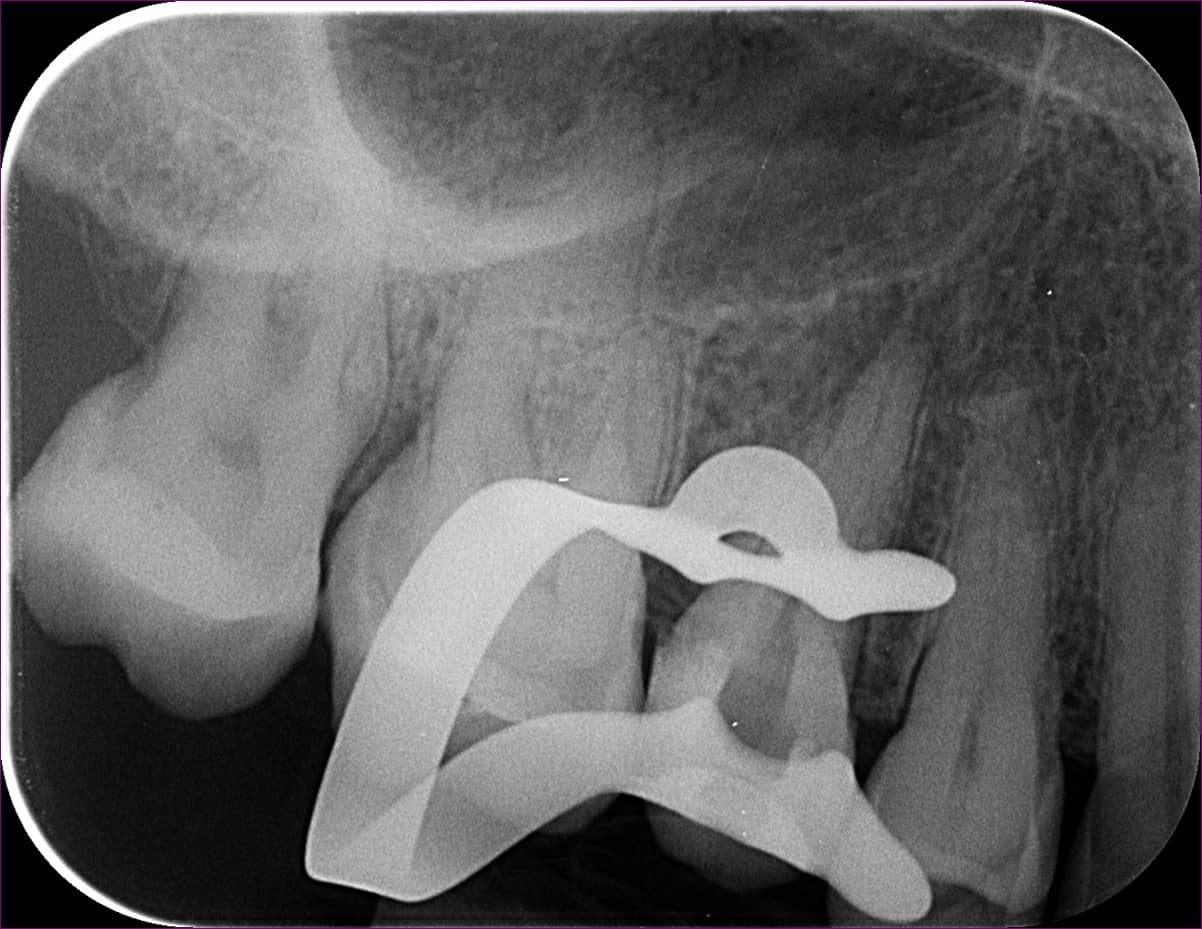

Először a szájpadlás felőli gyökércsatornában tártuk fel a tűt. Óvatosan, a megfelelő technikát alkalmazva sikerült eltávolítani a nagyjából 4 mm-es darabot. Ilyenkor készítünk egy kontrollröntgent, hogy lássuk, valóban nem maradt bent semmi az eltávolított tűből. Ekkor vált biztossá dr. Kovács Kitti gyanúja: van még egy műszer a fogban.

Mindkét fragmentumot sikerült eltávolítani